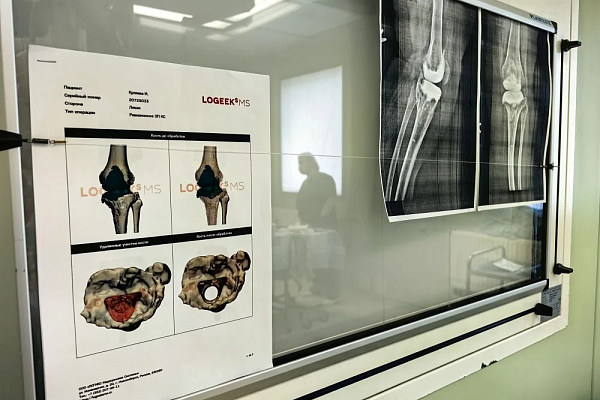

Лечение началось с санации очага воспаления - пациентке имплантировали временный антибактериальный спейсер. Параллельно начали подготовку к следующему этапу – ревизионному эндопротезированию.

Разрушенный инфекцией фрагмент большеберцовой кости требовал замещения. Чтобы восполнить её целостность, обратились к производителям 3D-протезов. На основе данных компьютерной томографии специалисты изготовили точную копию утраченного костного фрагмента. Операция по его установке и эндопротезированию сустава прошла успешно. Пациентка уже выписана и настроена на возвращение к полноценной активности.